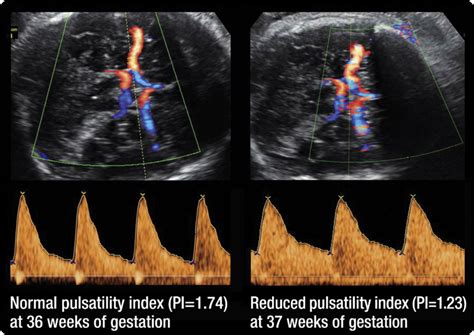

Doppler of the middle cerebral artery for the assessment of fetal well